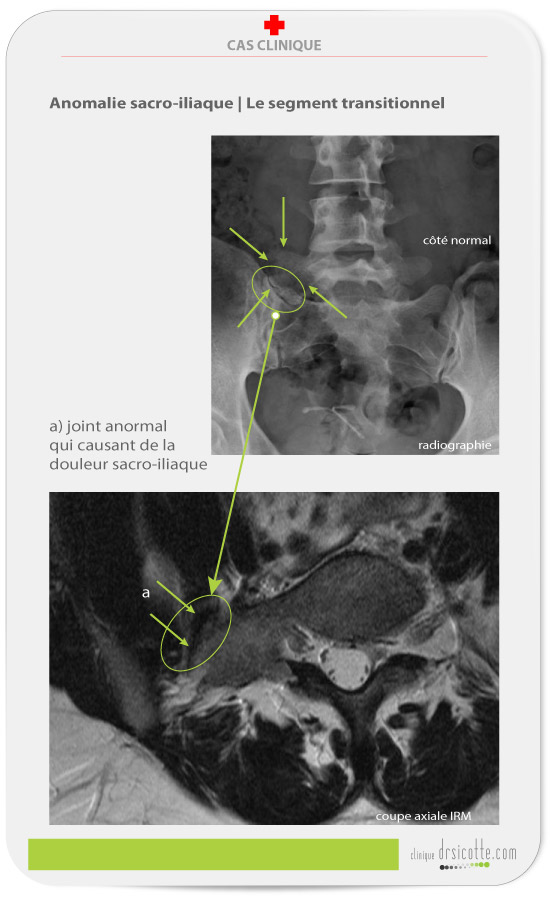

Faute d’amélioration notable dans un délai raisonnable de la douleur sacro-iliaque du patient (moins de 15 jours ou six traitements ou moins), le clinicien se doit d’investiguer une possible anomalie sacro-iliaque présente chez 4% à 30% de la population. Le segment transitionnel crée des dysfonctions biomécaniques importantes à la région lombaire. Voici la classification de Castellvi.

Pendant des années, cette patiente se plaignait de douleurs au bas du dos. Dans l’incapacité d’établir un diagnostic, le médecin traitant ferme le dossier. Pourtant, les imageries démontrent clairement la dysfonction.

Cette patiente nous consulte pour des douleurs lombaires et sacro-iliaques. L’étude de l’IRM démontre deux particularités : un disque intervertébral anormalement développé à la vertèbre S1 (première vertèbre sacrée) et une géométrie anormale des corps vertébraux. Après analyse de la coupe axiale de l’IRM (voir image ci-haut), on aperçoit un joint supplémentaire autre que le joint sacro-iliaque.

Nous soupçonnons une anomalie de type segment transitionnel. Nous demandons des radiographies pour confirmer le diagnostic.

- Le joint transitionnel altère la biomécanique des deux joints sacro-iliaques.

- Puisque l’articulation sacro-iliaque ne fonctionne pas normalement, la région lombaire a tendance à démontrer des anomalies : ici la patiente présente un important débalancement de tonus musculaire de chaque côté de la colonne vertébrale.